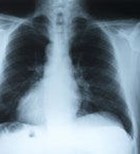

עישון הוא הגורם העיקרי לסרטן ריאות, מחלה אשר רק כ-15%...